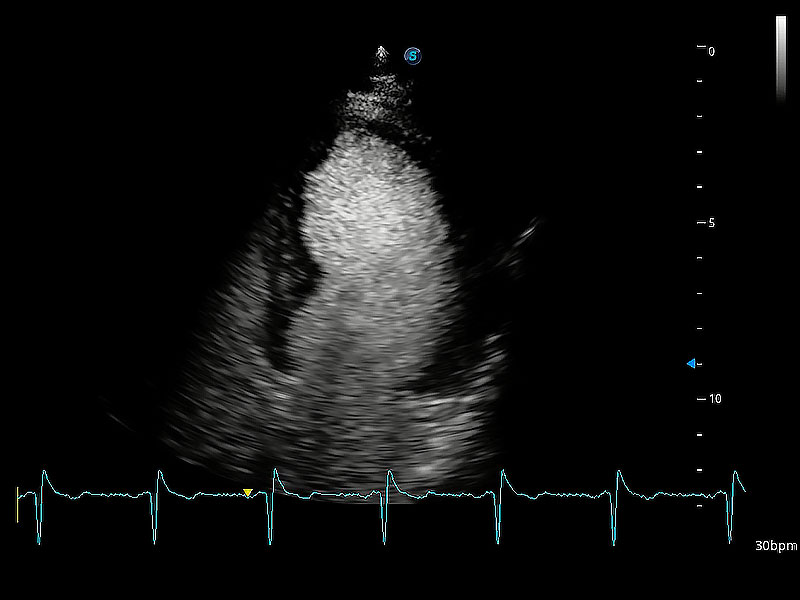

ProPet 80 配備了豐富的心臟探頭群、先進(jìn)的成像技術(shù)和專業(yè)的心臟測量工具,可幫助動物醫(yī)生為不同體型和生理結(jié)構(gòu)的動物提供心臟和心肌功能的全面評估。